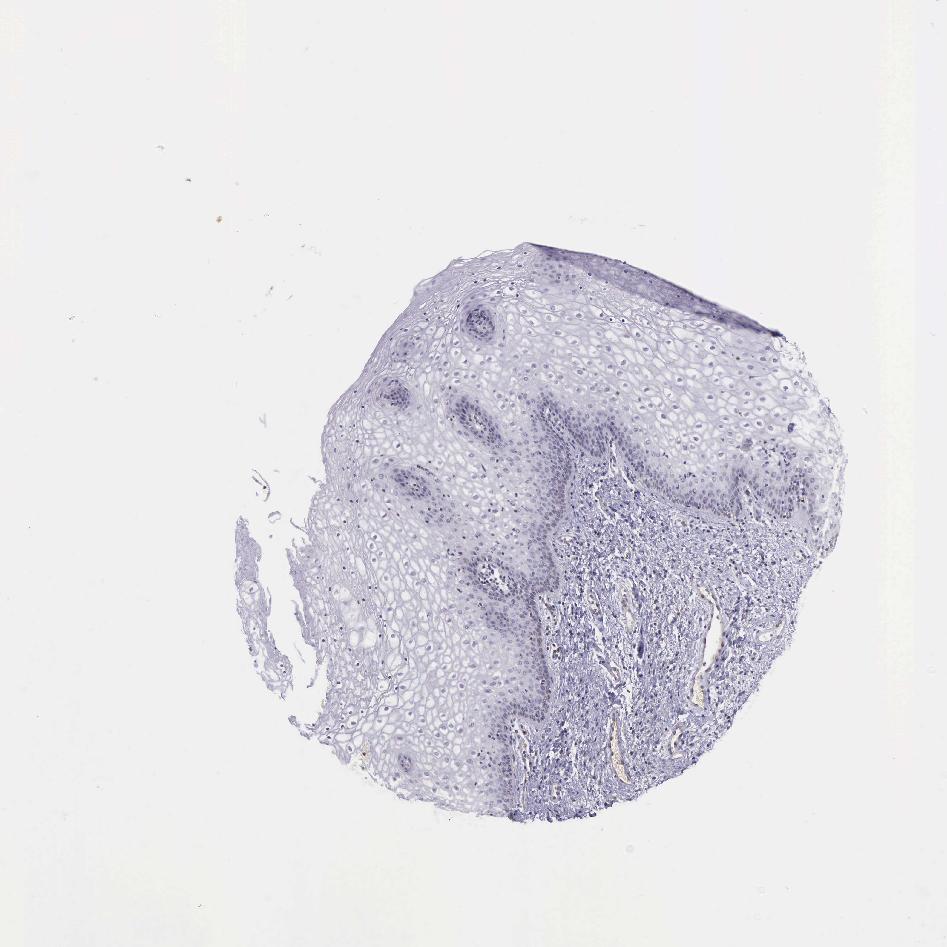

TISSUE PRIMARY DATA VAGINA Show tissue menu

VAGINA - Antibody stainingi

Antibody staining in the annotated cell types in the current human tissue is reported as not detected, low, medium, or high, based on conventional immunohistochemistry profiling in selected tissues. This score is based on the combination of the staining intensity and fraction of stained cells.

Each image is clickable and will lead to virtual microscopy that enables deeper exploration of all samples and also displays staining intensity scores, fraction scores and subcellular localization as well as patient and tissue information for each sample.

Antibody HPA045168Antibody CAB000147Antibody CAB003839Antibody CAB003840Antibody CAB075726Antibody CAB075727

Squamous epithelial cells HighNot detectedNot detectedMediumMediumMedium